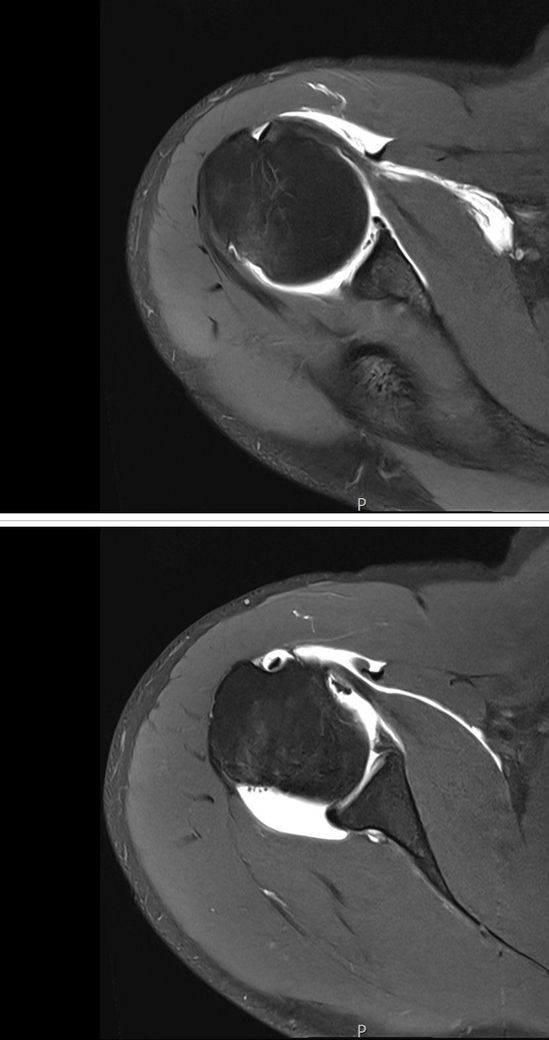

방카르트 병변 관절와순 파열정도 심한편인가요?

복싱이랑 운동이 취미이며 시합도 가끔 나갑니다 복싱하다가 5주 전 탈구가 있었고 어제 mra를 찍었는데 상태가 어떤 편인가요

비수술로 재활을 할 수 있을 정도인가요?

정밀한 소견은 올려주신 사진 이외에도 뱔개의 평가와 반복성여부를 종합하여 파악하는 것이 정확하고, 탈구 이후 방카르트 손상 소견은 일반적으로 흔히 나타날 수 있는 소견입니다.

비수술적인 재활이 충분히 가능하신 정도일 수 있지만, 재발위헌도에 따라 다를 수 있으므로 이점에 관련해서는 전문의 진료를 받아보신 후 소견을 참고하시는 것이 정확합니다.

사진 직접 판독은 불가하지만, 복싱 후 “탈구 5주 + MRA 촬영“이면 보통 관절순.인대 손상 여부를 보는 단계입니다.

관절순 파열이 크지 않고 불안정성 없으면 “비수술 재활로 가는 경우도 많습니다.“

사진보니까 가벼운 손상이 아니라 어깨 테두리 관절이 크게 떨어진 상태에요. 탈구하면서 구조물이 제대로 찢어진 상황이라어깨를 잡아주는 힘이 많이 약해져있어요. 복싱처럼 팔을 크게쓰고 충격 많은 운동을 계속하면 다시 빠질 가능성이 높고, 한번 더 빠지면 손상이 더 커질수 있어요. 일상생활만 하면 재활로 버틸수 있는 경우도 있지만 시합까지 하는 운동선수라면 재탈구 가능성이 높아서 수술을 권하는 경우가 많아요. 지금 상태로 무리해서 운동하는건 솔직히 좀 위험한 상황이에요.. 지금 스트레칭은 통증 없는 범위면 괜찮지만,

다만 지금과 같이 관절와순 파열은 확인이 되지만 추가적으로 뼈의 결손이 있는지 추가 확인을 해보시길 바랍니다.

현재로썬 비수술 치료를 통해 먼저 재활을 해보시고 호전이 없거나 습관성 탈구, 움직임 제한, 통증 등 악화가 일어난다면 수술을 고려 해보시길 바랍니다.